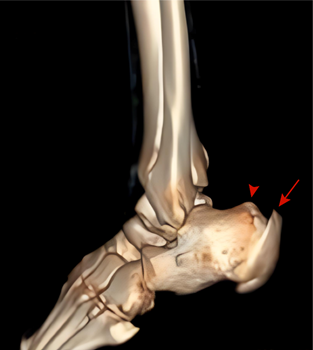

图6:CT检査(3D重建)可见跟腱止点处钙化增生(长箭头), 跟骨后上突增生(箭头)